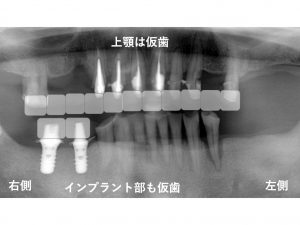

以下は

下顎右側の奥歯にインプラントを埋入した直後です。

少しでも早く、噛めるようにすることが大切です。

インプラント埋入と同時に仮歯を作成しました。

この時点で

上顎はすでに仮歯となっています。

そのため、噛むことや審美的なことには問題は生じていません。

この時点では、

下顎の左側の奥歯は抜歯していません。

インプラントを埋入するまでは、

左側の奥歯では噛む部分がありませんので

インプラントを埋入し、仮歯で噛めるようになるまで

下顎左側の奥歯は、抜歯せずに

そのまま残してあります。

こうした対応を行うことで

治療期間中の噛むことの問題を軽減させます。